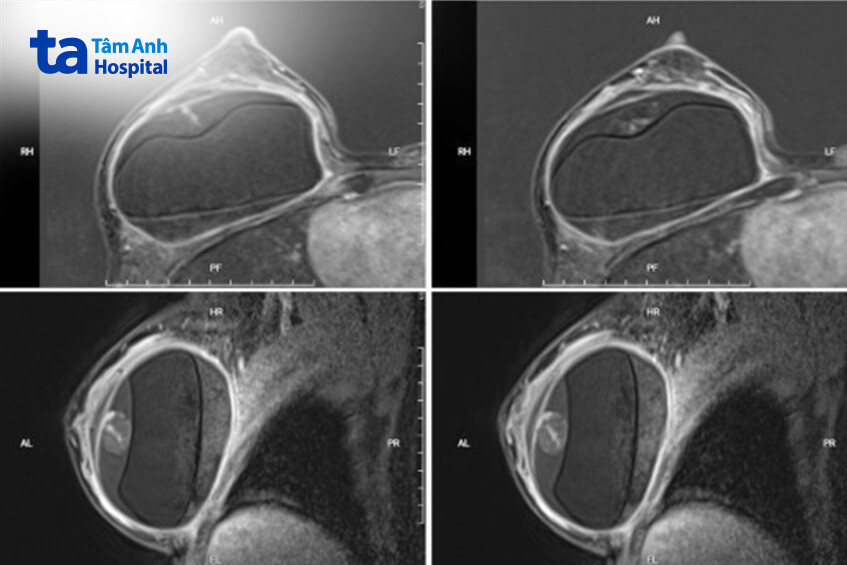

Chị Thành được chỉ định siêu âm và chụp cộng hưởng từ (MRI). Hình ảnh MRI cho thấy túi hai bên còn nguyên vẹn. Ngực bên trái ghi nhận có tụ dịch không thuần nhất quanh túi ngực trái. Bệnh nhân sau đó được chỉ định chọc hút dịch xét nghiệm tế bào học, kết quả cho thấy dịch viêm chẩn đoán phân biệt với u lympho tế bào lớn thoái sản liên quan túi ngực (BIA-ALCL), một dạng ung thư hiếm gặp có thể xuất hiện sau hơn 10 năm phẫu thuật nâng ngực.

Quá trình thăm khám cho thấy vú phải của chị Thắm có các dấu hiệu căng tức, biến dạng, nghi ngờ co thắt bao xơ túi ngực, vỡ túi ngực. Kết quả MRI phát hiện vỡ túi hai bên kèm tụ máu quanh, silicone rò ra mô xung quanh.